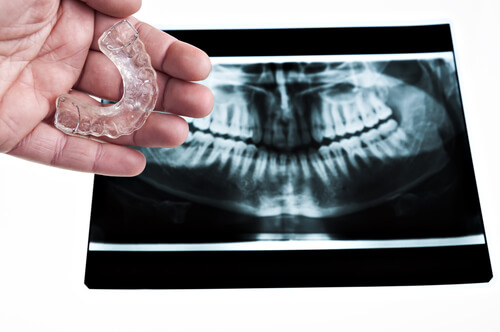

Per combattere le conseguenze del bruxismo, si può ricorrere all’utilizzo di protettori per la bocca (paradenti) che alleviano la pressione esercitata quando si stringono o si digrignano i denti; oltre a ciò, è possibile ricorrere a massaggi rilassanti dei muscoli del viso, soprattutto della zona di mandibola, collo e spalle.